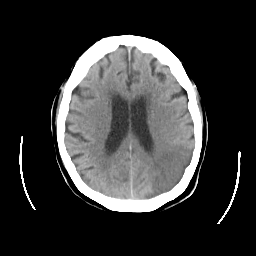

CT Study #2 -- Slice #18